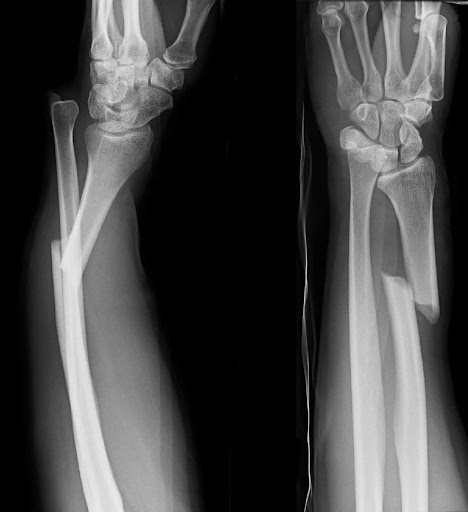

Displaced

when the bone has broken and the broken ENDS are NO LONGER ALIGNED

it has been “displaced”

misalignment